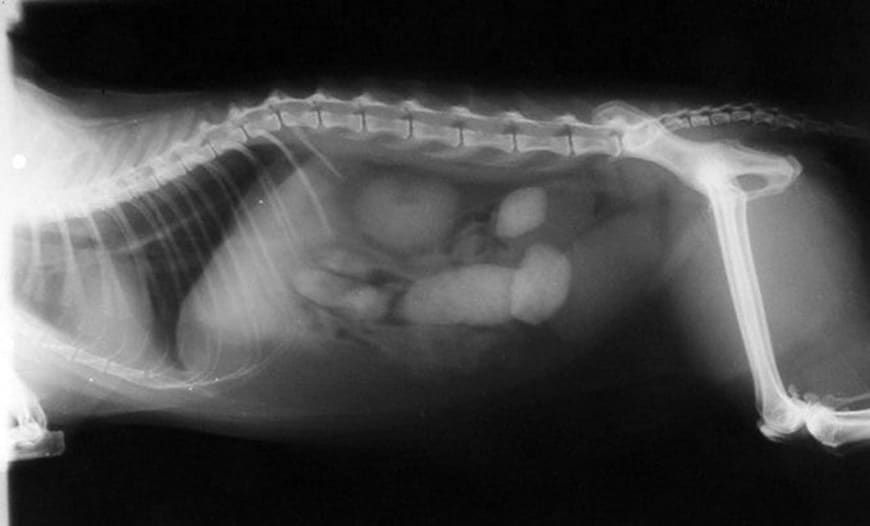

Шарики из шерсти (трихобезоары) – это образования, состоящие из скоплений шерсти, которая не смогла выйти из организма естественным путем. Они могут задерживаться в желудке или тонком кишечнике кота, вызывая неприятные ощущения и даже серьезные проблемы со здоровьем.

Во время вылизывания коты неизбежно проглатывают часть своей шерсти. Поскольку шерсть состоит из кератина – белка, который не переваривается желудком, шерсть не расщепляется и не растворяется в желудочно-кишечном тракте. Обычно небольшое количество шерсти проходит через пищеварительный тракт и выводится с фекалиями. Однако, если шерсти накапливается слишком много, она может слипнуться в плотные комочки или шарики — трихобезоары.

— медикаментозное лечение. Некоторые лекарства помогают расщеплять шерсть или способствуют ее выходу естественным путем.

— хирургическое вмешательство. В редких случаях, когда шарики из шерсти становятся слишком большими и блокируют кишечник, может потребоваться хирургическое вмешательство.